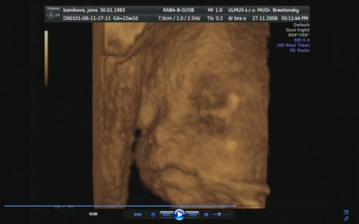

30.10.2008 - výsledky skríningových testov dopadli na jednotku, veľmi sa tešíme a dňa *****27.11.2008 - sme sa objednali na 3D ultrazvuk, tak som zvedavá, či nám potvrdia dievčatko a uvidím to na vlastné oči ... všetkým sa akosi zdá, že to bude chlapec 🙂 ....

Tak a máme to za sebou, náš 3D ultrazvuk, na ktorý sme sa moc moc tešili, bolo to úžasné, naša bambula Simonka sa nám ukázala v plnej kráse, akurát si zakrývala tváričku a nie a nie sa nám ukázať ... ale pár fotiek sa predsa len podarilo..pán doktor všetko prezrel a zatiaľ sa všetko vyvíja tak ako má .....